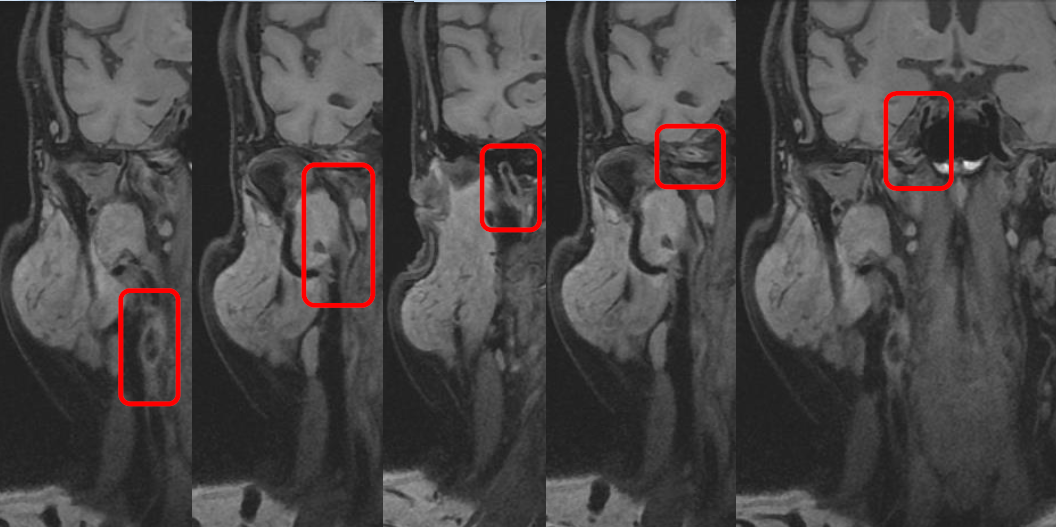

影像诊断

颅脑DWI

病历夹什么径技·第152期|串联营病历夹:川陕大营_https://www.jmylbn.com_新闻资讯_第40张

病历夹什么径技·第152期|串联营病历夹:川陕大营_https://www.jmylbn.com_新闻资讯_第41张

<<滑动查看下一张图片>>

诊断:右侧放射冠区急性脑梗死。

颈部血管高分辨

病历夹什么径技·第152期|串联营病历夹:川陕大营_https://www.jmylbn.com_新闻资讯_第42张

诊断:右侧颈内动脉近端腔内异常改变,考虑夹层可能,右侧颈内动脉C1-C4管壁弥漫性增厚,管腔窄。

脑灌注成像

病历夹什么径技·第152期|串联营病历夹:川陕大营_https://www.jmylbn.com_新闻资讯_第43张

病历夹什么径技·第152期|串联营病历夹:川陕大营_https://www.jmylbn.com_新闻资讯_第44张

病历夹什么径技·第152期|串联营病历夹:川陕大营_https://www.jmylbn.com_新闻资讯_第45张

诊断:右侧额顶颞叶及基底节区局部血流灌注减低,请结合临床。